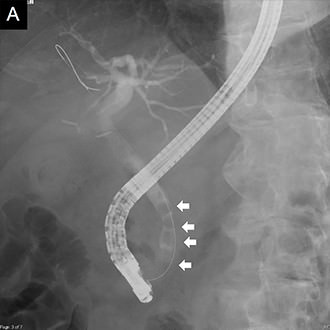

図4 総胆管結石の内視鏡治療

総胆管結石の内視鏡的な完全除去が可能でした。

A. 内視鏡的胆管造影で複数の総胆管結石を確認しました (↓)。

B. 乳頭切開を行い、全結石を除去しました。

• 内視鏡治療画像:内視鏡的胆管造影で複数の総胆管結石を確認

• 内視鏡治療画像:乳頭切開を行い、全結石を除去